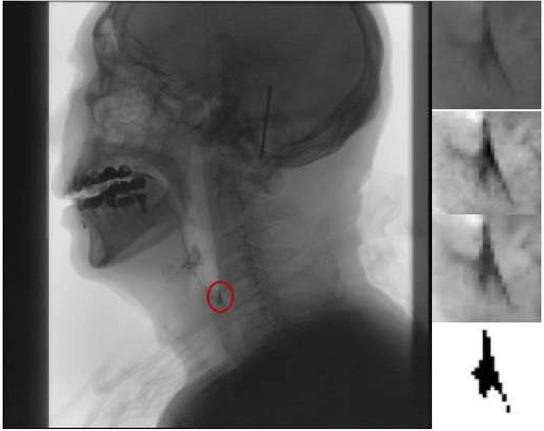

images

Figure 1 (a) Oral preparatory phase. Fluid barium is injected into the mouth through a syringe (b) Oral phase (<11.5). Trigger swallowing reflex (c) Phary geal phase (<1 s). trigger ring pharynx muscle (d) Esophageal phase. The pharyngeal contraction, the fluid extract into the esophagus.

However, due to the lack of chewing process based on the swallowing observation of fluid barium, and the swallowing speed of fluid barium is ten times faster, usually 12 s fluid through, so it is crucial to observe the flow of barium in stages, tracheal aspiration and observe the change of residual quantity in this experiment.